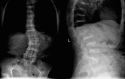

Alkaptonuria

Keywords: Alkaptonuria; Homogentisic acid; Ochronosis.